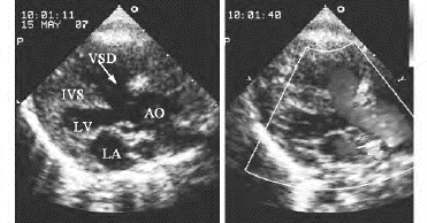

图17-2 法洛四联症二维超声图像

右室流出道长轴切面,显示嵴下型室间隔缺损、右室流出道狭窄及肺动脉辨狭窄

漏斗部狭窄可分为:①局限性狭窄。表现为右室流出道前壁及室间隔局部向流出道腔内突起肌性回声,导致流出道局部径小。狭窄远端流出腔与狭窄的肺动脉瓣环或瓣叶之间形成第三心室,通常较小。②广泛性狭窄。表现为室间隔与右室流出道前壁普遍性肥厚,导致流出道内径普遍性不同程度变小(图17-2)。

肺动脉瓣狭窄:表现为瓣叶回声增强、增厚、短小,开放受限或呈圆顶状突向肺动脉腔内(图17-2)。严重者肺动脉瓣叶可无开放运动,呈闭锁状态。亦可伴有肺动脉主干狭窄后扩张。

(2)室间隔缺损:左心室长轴及五腔等切面,显示主动脉前壁与室间隔连续中断(图17-1左图)。多数为较大的嵴下型缺损,直径一般在1.5~3.0cm,大血管短轴切面,相当于时钟9:30至12:00位置;肺动脉瓣下缺损较少见,大血管短轴切面相当于时钟12:00至2:00位置(与肺动脉瓣位置有关),缺损上缘达肺动脉环部,此型常不显示室上嵴结构。